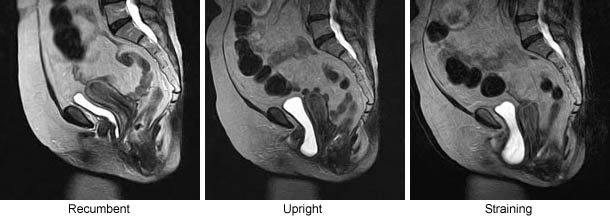

Case#: 8       MRI Visualization of Position-Dependent Changes in the Pelvis: Pelvic Floor Dysfunction (PFD)

Inferior prolapse of the bladder and uterus (PFD)(5 cm) is visualized in the Upright Weight-Bearing Position that is not visualized in the recumbent position.